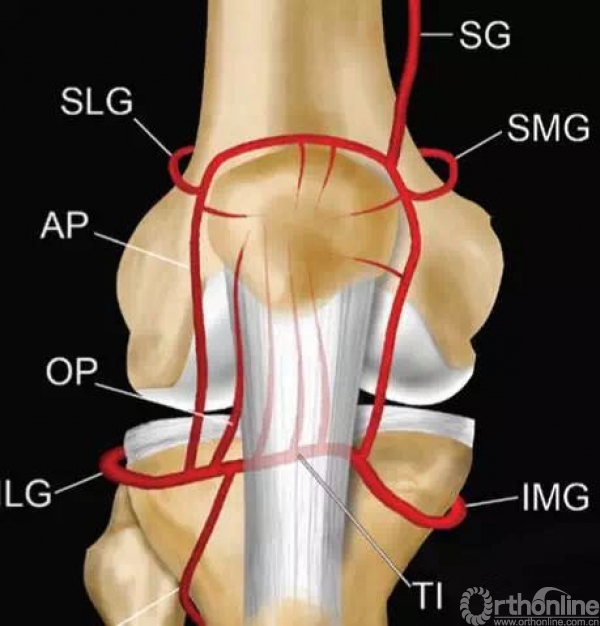

3.髌骨的血供在哪里?——主要来源于髌骨下级。